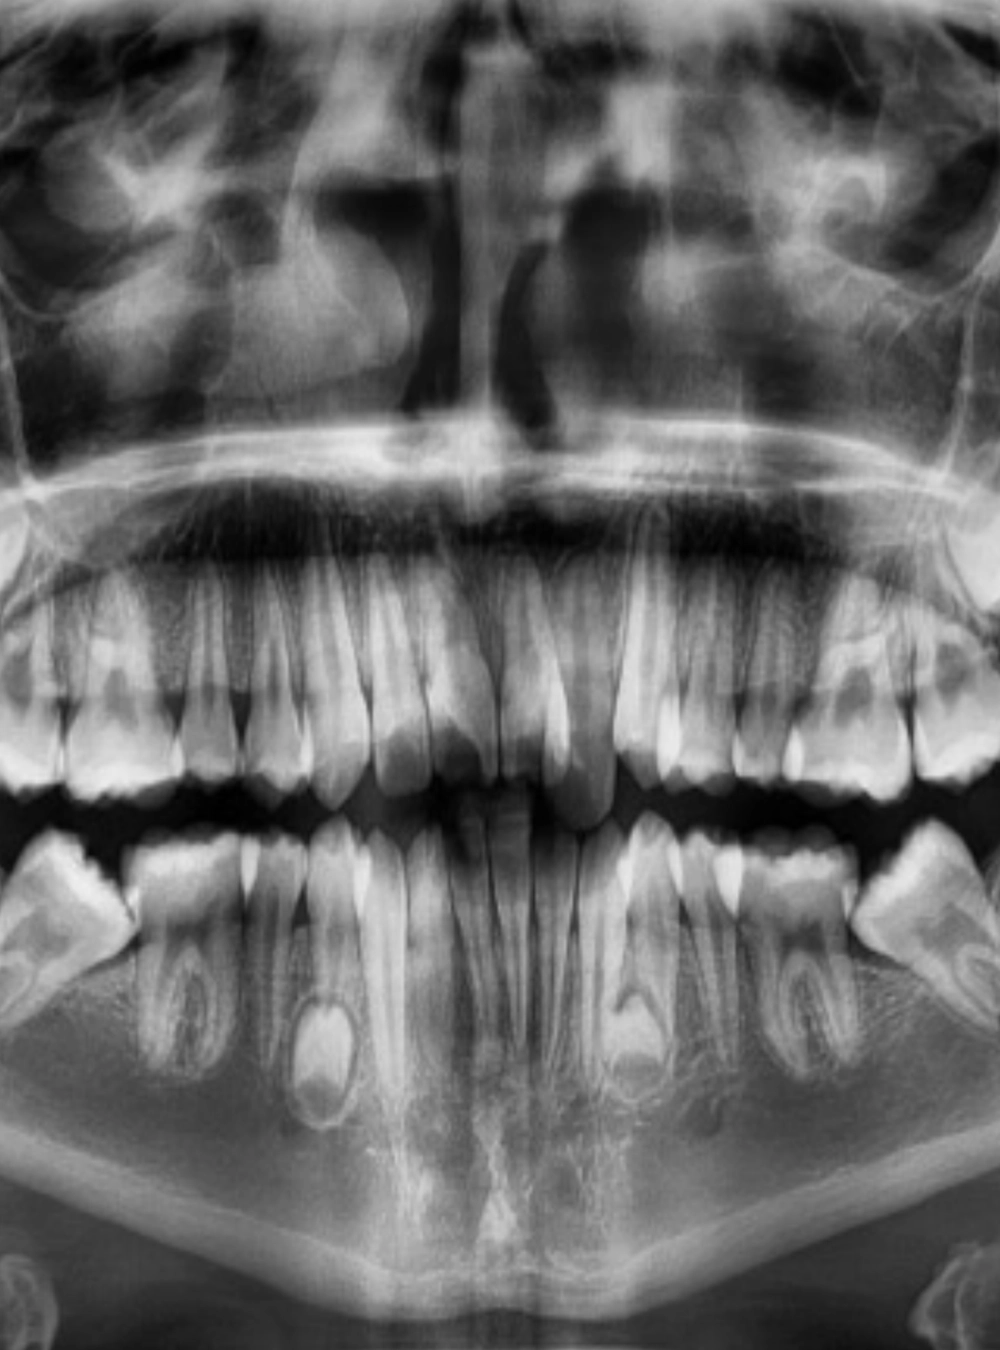

Radiología Dental

El sistema de radiografias digital permite obtener imágenes en segundos.

El estudio de ortodoncia es el primer paso que se debe realizar antes de colocarse la aparatología necesaria para corregir la posición de los dientes.